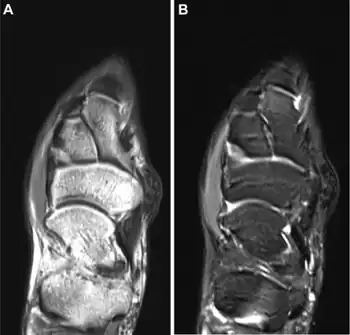

| a,b)MRI appearance of surfers' knot medial to the persons' navicular | |